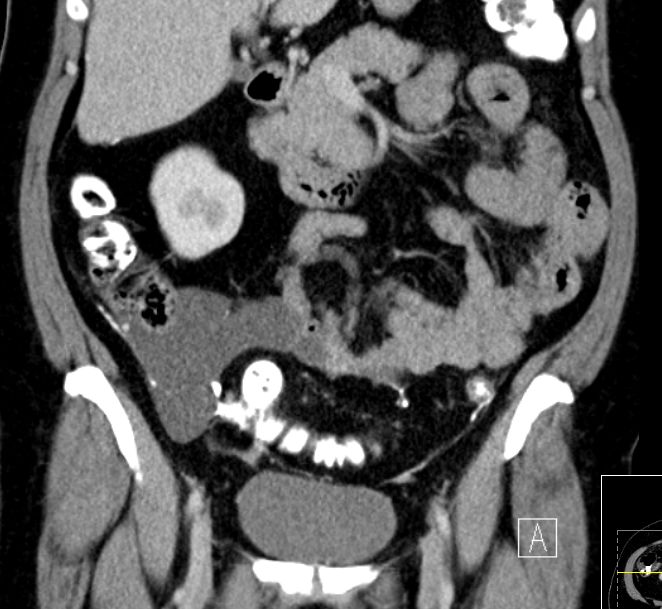

| Fall 1 | 51-jährige Frau mit primärem Peritonealkarzinom. | |||

| Therapie: Partielle Peritonektomie, HE mit Adnexen, Sigmaresektion (Hartmann), Omentumresektion. | Histologisch: Gut differenziertes seröses Adenokarzinom mit massenhaft Psammomkörperchen (Psammokarzinom). G1.Staging: pT3c. | |||